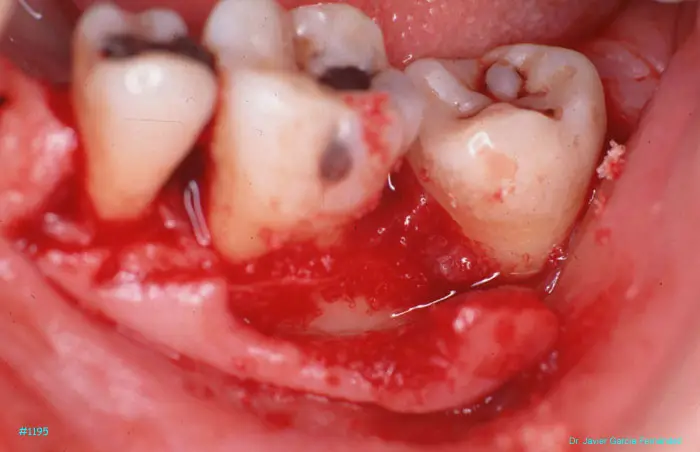

Atlas of Surgical Techniques in Periodontics. Chapter III. Atlas de Técnicas Quirúrgicas en Periodoncia